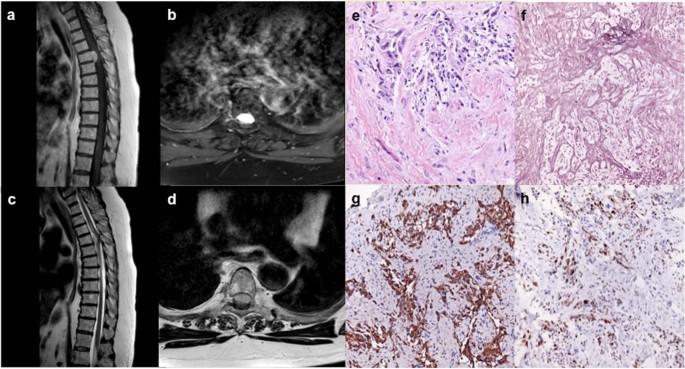

Six months after completion of chemotherapy, she presented with increasing gait instability of two weeks duration and worsening thoracic back pain, localized between her shoulder blades. MRI of her thoracic and lumbar spine was obtained, demonstrating a homogenously enhancing dural-based, extramedullary lesion anterior to the spinal cord at T4 with moderate cord compression, causing edema extending from T2 to T7 (Fig. 2a–d). She was neurologically intact on examination other than brisk lower extremity reflexes, allodynia at the T4 level, and baseline right-sided hemibody numbness. Imaging findings were consistent with spinal meningioma, and the patient was admitted with plans for elective, inpatient surgery. However, two days after admission, she developed acute weakness in her bilateral lower extremities and subsequently was taken to the operating room for urgent resection of her tumor, which was removed in its entirety. Intra-operatively, the tumor was noted to be dural-based with a well-defined plane between tumor and the dura as well as the pia of the spinal cord. Motor evoked and somatosensory evoked potentials were improved at the end of the case, compared to baseline levels. Final pathology from the resected specimen was WHO IV gliosarcoma with biphasic tissue architecture, comprised of prominent GFAP-positive glial regions admixed with GFAP-negative spindled areas containing reticulin fibers (Fig. 2e–h). The Ki-67 index was elevated >10–15% and further routine molecular testing demonstrated MGMT promoter methylation but was otherwise negative for IDH1 mutation and ATRX loss.

a Representative sagittal and (b) axial slices from T1-weighted MRI after contrast administration show a homogeneously enhancing intradural, extramedullary lesion anterior to the spinal cord at the T4 level with associated cord compression seen on (c) sagittal and (d) axial slices on T2-weighted MRI. e Biphasic architecture is seen on hematoxylin & eosin staining, including (f) reticulin rich sarcomatous regions, interspersed with (g) GFAP-positive glial regions, and (h) an elevated Ki-67 proliferative index of ~10–15%.